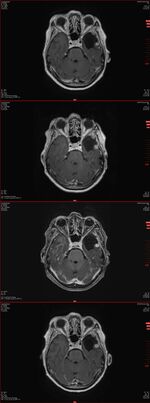

30.03.2017: OP

• Komplette Resektion des ausgedehnten links temporalen Meningeoms (Neurochirurgie Bremen).

initiale Histologie: Meningeoms WHO-Grad II.

Schön zu sehen war, dass der bestrahlte Tumor kein Wachstum hatte - siehe Bilder vor dem Text.